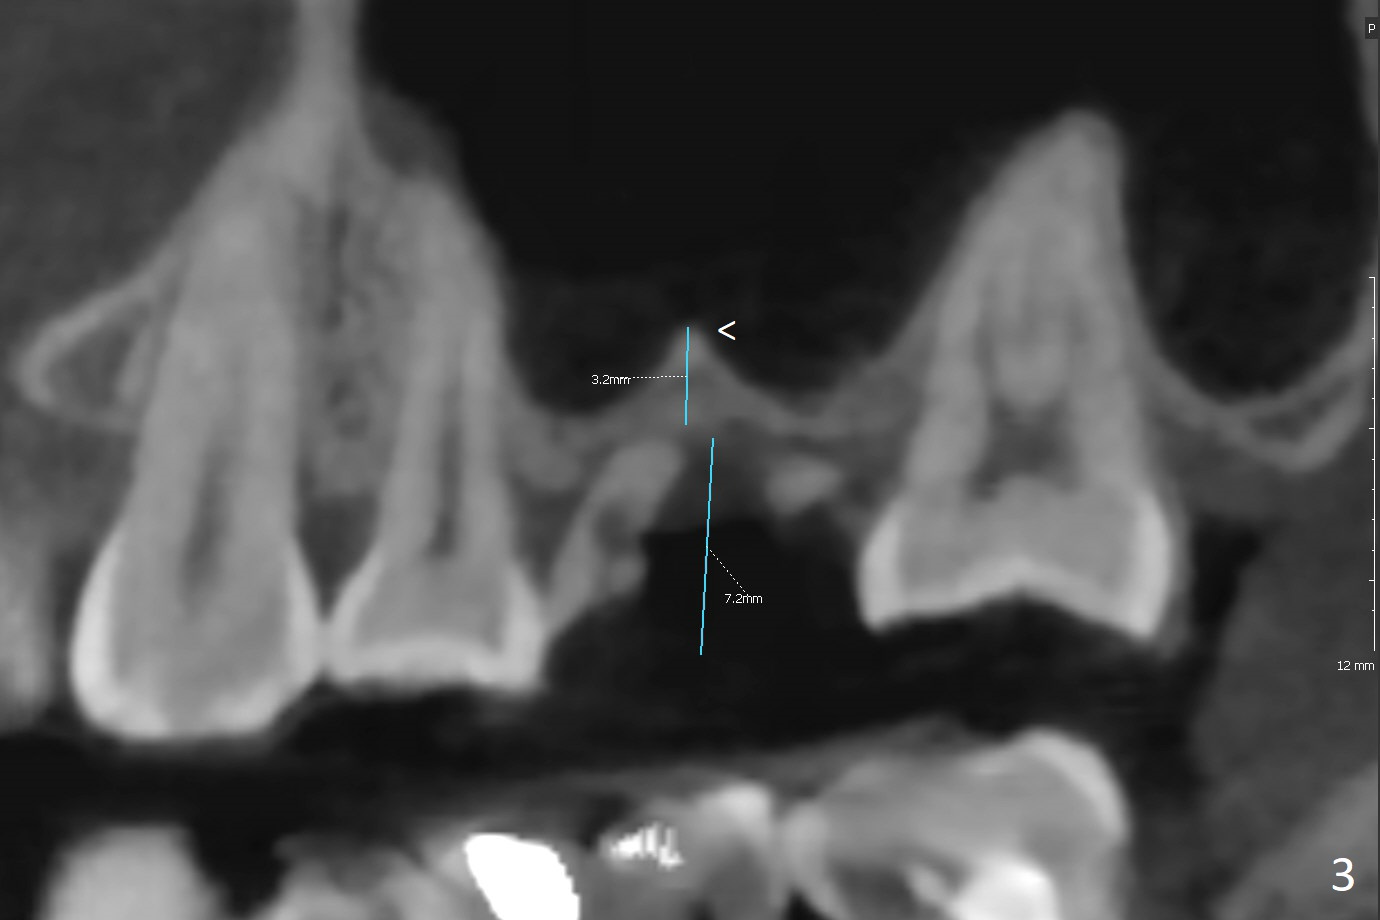

A 36-year-old woman is nervous about dentistry. She will take Valium by herselft before surgery (Fig.1). The tooth #3 has 3 residual roots (Fig.2 (CBCT 3 D occlusal view)). The bone is 2-3 mm thick (Fig.3,4 (sagittal, coronal sections)). A 5x7.3 mm implant will be placed with IS guide (Fig.5 (12 mm offset)). Since IBS implants are able to achieve amazing stability in the thin bone, prepare the shortest 4-5 mm in diameter dummy implants (IS (better surface treatment) and IBS) after sinus lift using UF Guided Sinus Lift Approach Kit (surgery). With intact tooth structure at #14, the bone height is not much (Fig.6), congenital (genetic) in nature. The infection at #31 is more severe (Fig.7). Extraction will be the 2nd in order. Because of limited bone, it is better to do bone graft first. The patient is concerned about the discolored upper right canine, which should be associated with orthodontics 20 years ago (take photos). The apical canal is obliterated (Fig.8,9 arrow) with periapical radiolucency (arrowhead). In fact the bone at #31 is so little that the tooth will be extracted for socket preservation.